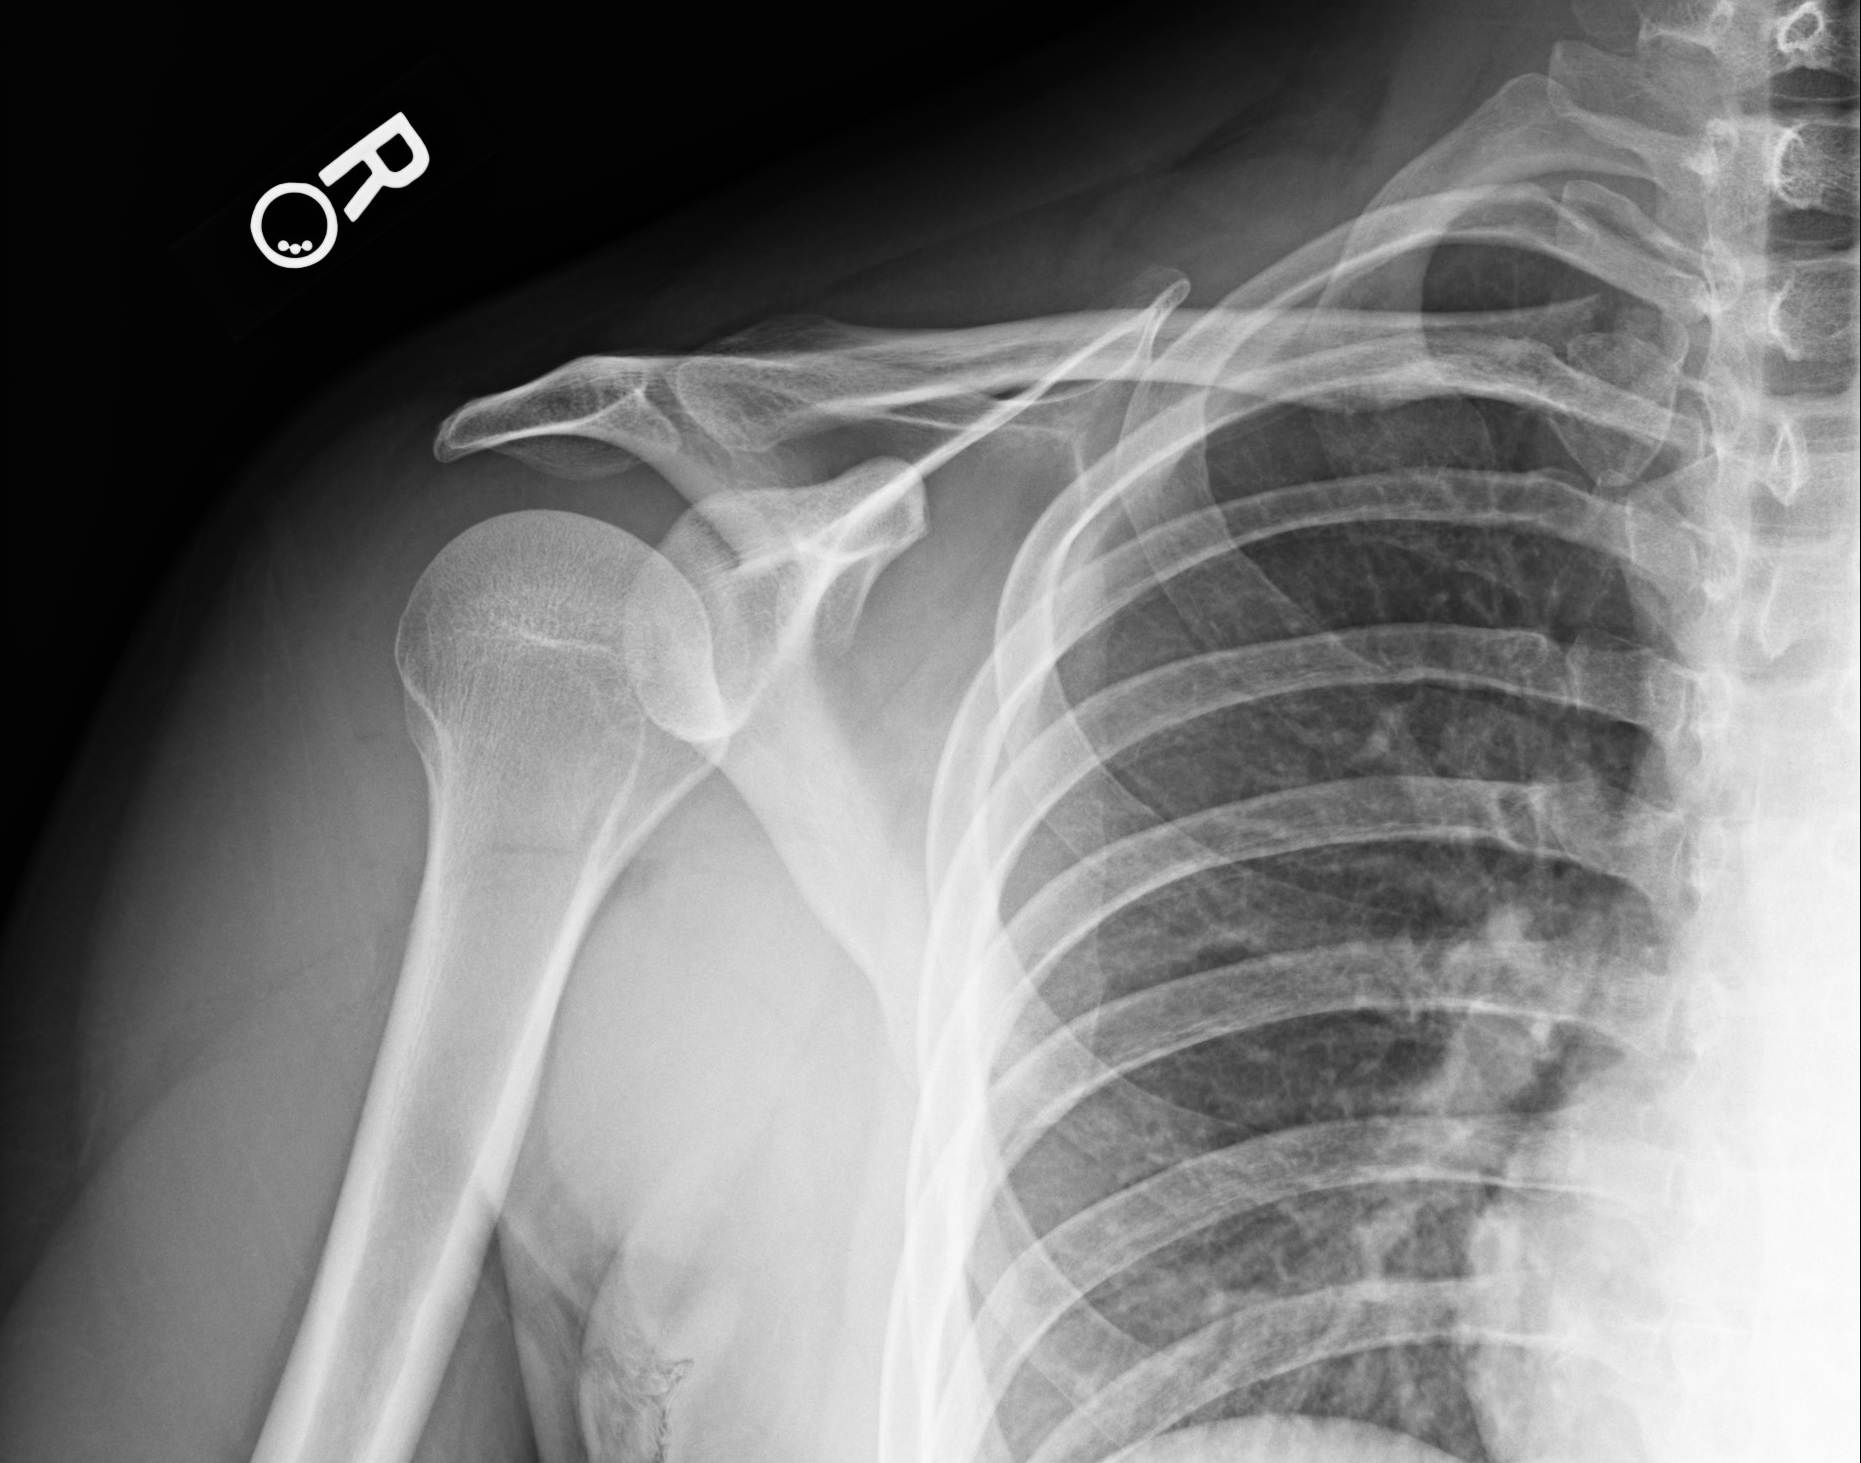

Radiographs of the right shoulder were taken (Figures 1-3).

Figure 1. Anteroposterior view of right shoulder, internal rotation.